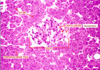

How to differentiate zones of the cortex of the adrenal gland?

The zona fasiculata is much more pale staining and you see empty space here. The zona fasciculata cells have lipid components and this is extracted during staining. This is why it looks white. But these cells are also much more puffy looking compared to the cells around them. And finally over here is the zona reticularis.

In the zona fasciculata the cells are in straight cords, in the reticularis you can see much more branching rather than straight lines.